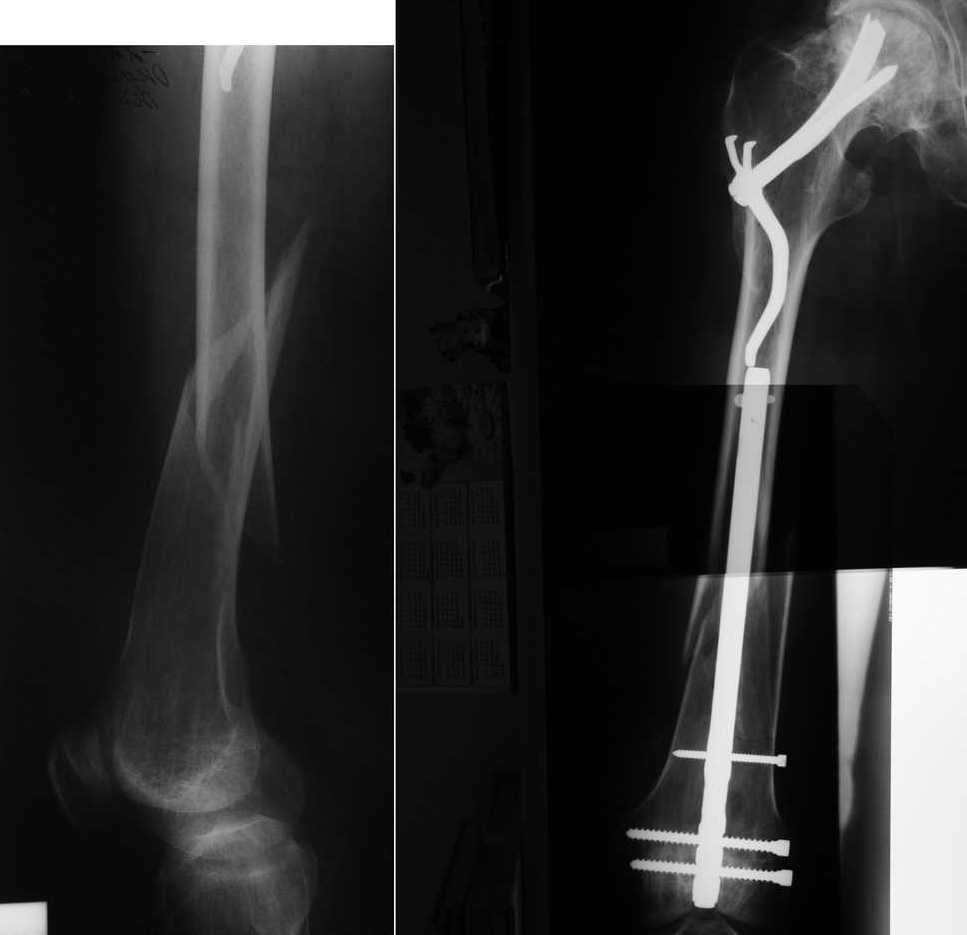

Хотим напомнить о забытом, эффективном методе остеосинтеза медиальных переломов шейки бедренной кости. Пациенту 55 лет был выполнен остеосинтез медиального перелома шейки бедренной кости фиксатором Сеппо 15 лет назад. В течение этих лет пациент жил не тужил, пока в марте сего года не получил перелом диафиза этого же бедра. Мы сочли единственно возможным применение в данной ситуации метода остеосинтеза штифтом с ретроградным введением. С удовольствием выслушаем ваши мнения. Возможно у кого-то ещё есть опыт применения фиксаторов Сеппо. Доктор Головач О. Н., доктор Савочкина М. А., г. Дзержинский, Подмосковье.